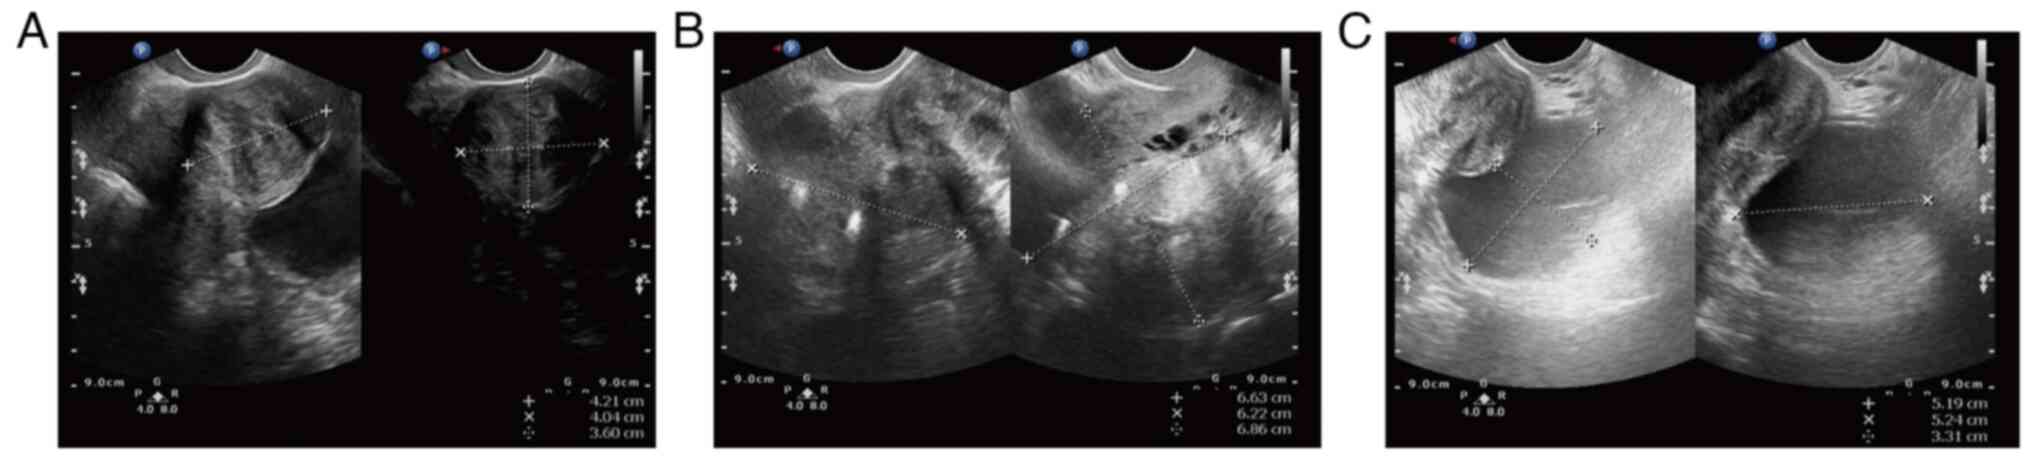

The patient was a 47-year-old married woman who complained of a pelvic mass during a physical examination a month ago (February, 2021). The preoperative transvaginal ultrasound displayed multiple inhomogeneous hypoechoic echoes without obvious blood flow signals in the uterine myometrium (the largest one on the right uterine wall, which occludes the right ovary; Fig. 1A and B). There was a 52x52x33 mm well-circumscribed anechoic spot in the left ovary without an obvious blood flow signal (Fig. 1C). Several anechoic spots were detected in the cervix, with a maximum diameter of 8 mm. The endometrium measured ~5 mm in thickness. Cervical liquid-based cytology (Thinprep cytologic test, TCT) was negative for intraepithelial lesions or malignant lesions and the high-risk HPV test was negative. The patient underwent left adnexectomy; a frozen section of the left ovarian revealed a mucinous borderline tumor. The patient underwent a rapid cytological examination of the peritoneal washing fluid and no tumor cells were found. Intraoperative examination of the appendix and other digestive tract organs showed no obvious abnormality. Total abdominal hysterectomy and bilateral salpingo-oophorectomy were subsequently performed.

Figure 1

Ultrasound images. (A) Multiple inhomogeneous hypoechoic echoes without obvious blood flow signals between the uterine muscle. (B) The uterus was measured ~69x66x62 mm. (C) A 52x52x33 mm anechoic area is visible in the left ovary without an unmistakable blood flow signal.